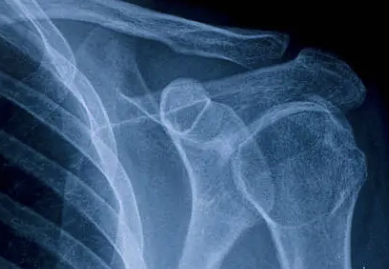

어깨통증을 진단하는 데 가장 중요한 검사는? X-Ray검사!

어깨 통증을 진단하는 데 가장 중요한 검사는 X-ray 검사입니다.

X-ray 검사는 어깨 질환을 진단하는 가장 기본적인 검사 방법으로, 통증의 원인과 양상을 파악하는 데 도움이 됩니다.

하지만 X-ray 검사만으로는 모든 어깨 질환을 정확히 진단하기 어려울 수 있기 때문에 다음과 같은 추가 검사들이 필요할 수 있습니다.